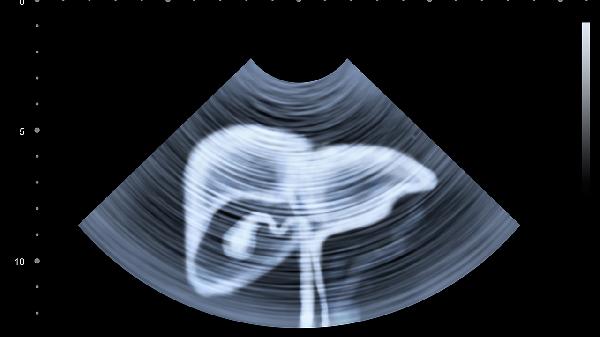

膽囊炎或膽石癥可能引起右側肩胛區牽涉痛,少數表現為左側疼痛。疼痛常于進(jìn)食油膩食物后發(fā)作,伴有惡心、腹脹等消化道癥狀。腹部超聲檢查可確診,需低脂飲食并規范治療原發(fā)病。